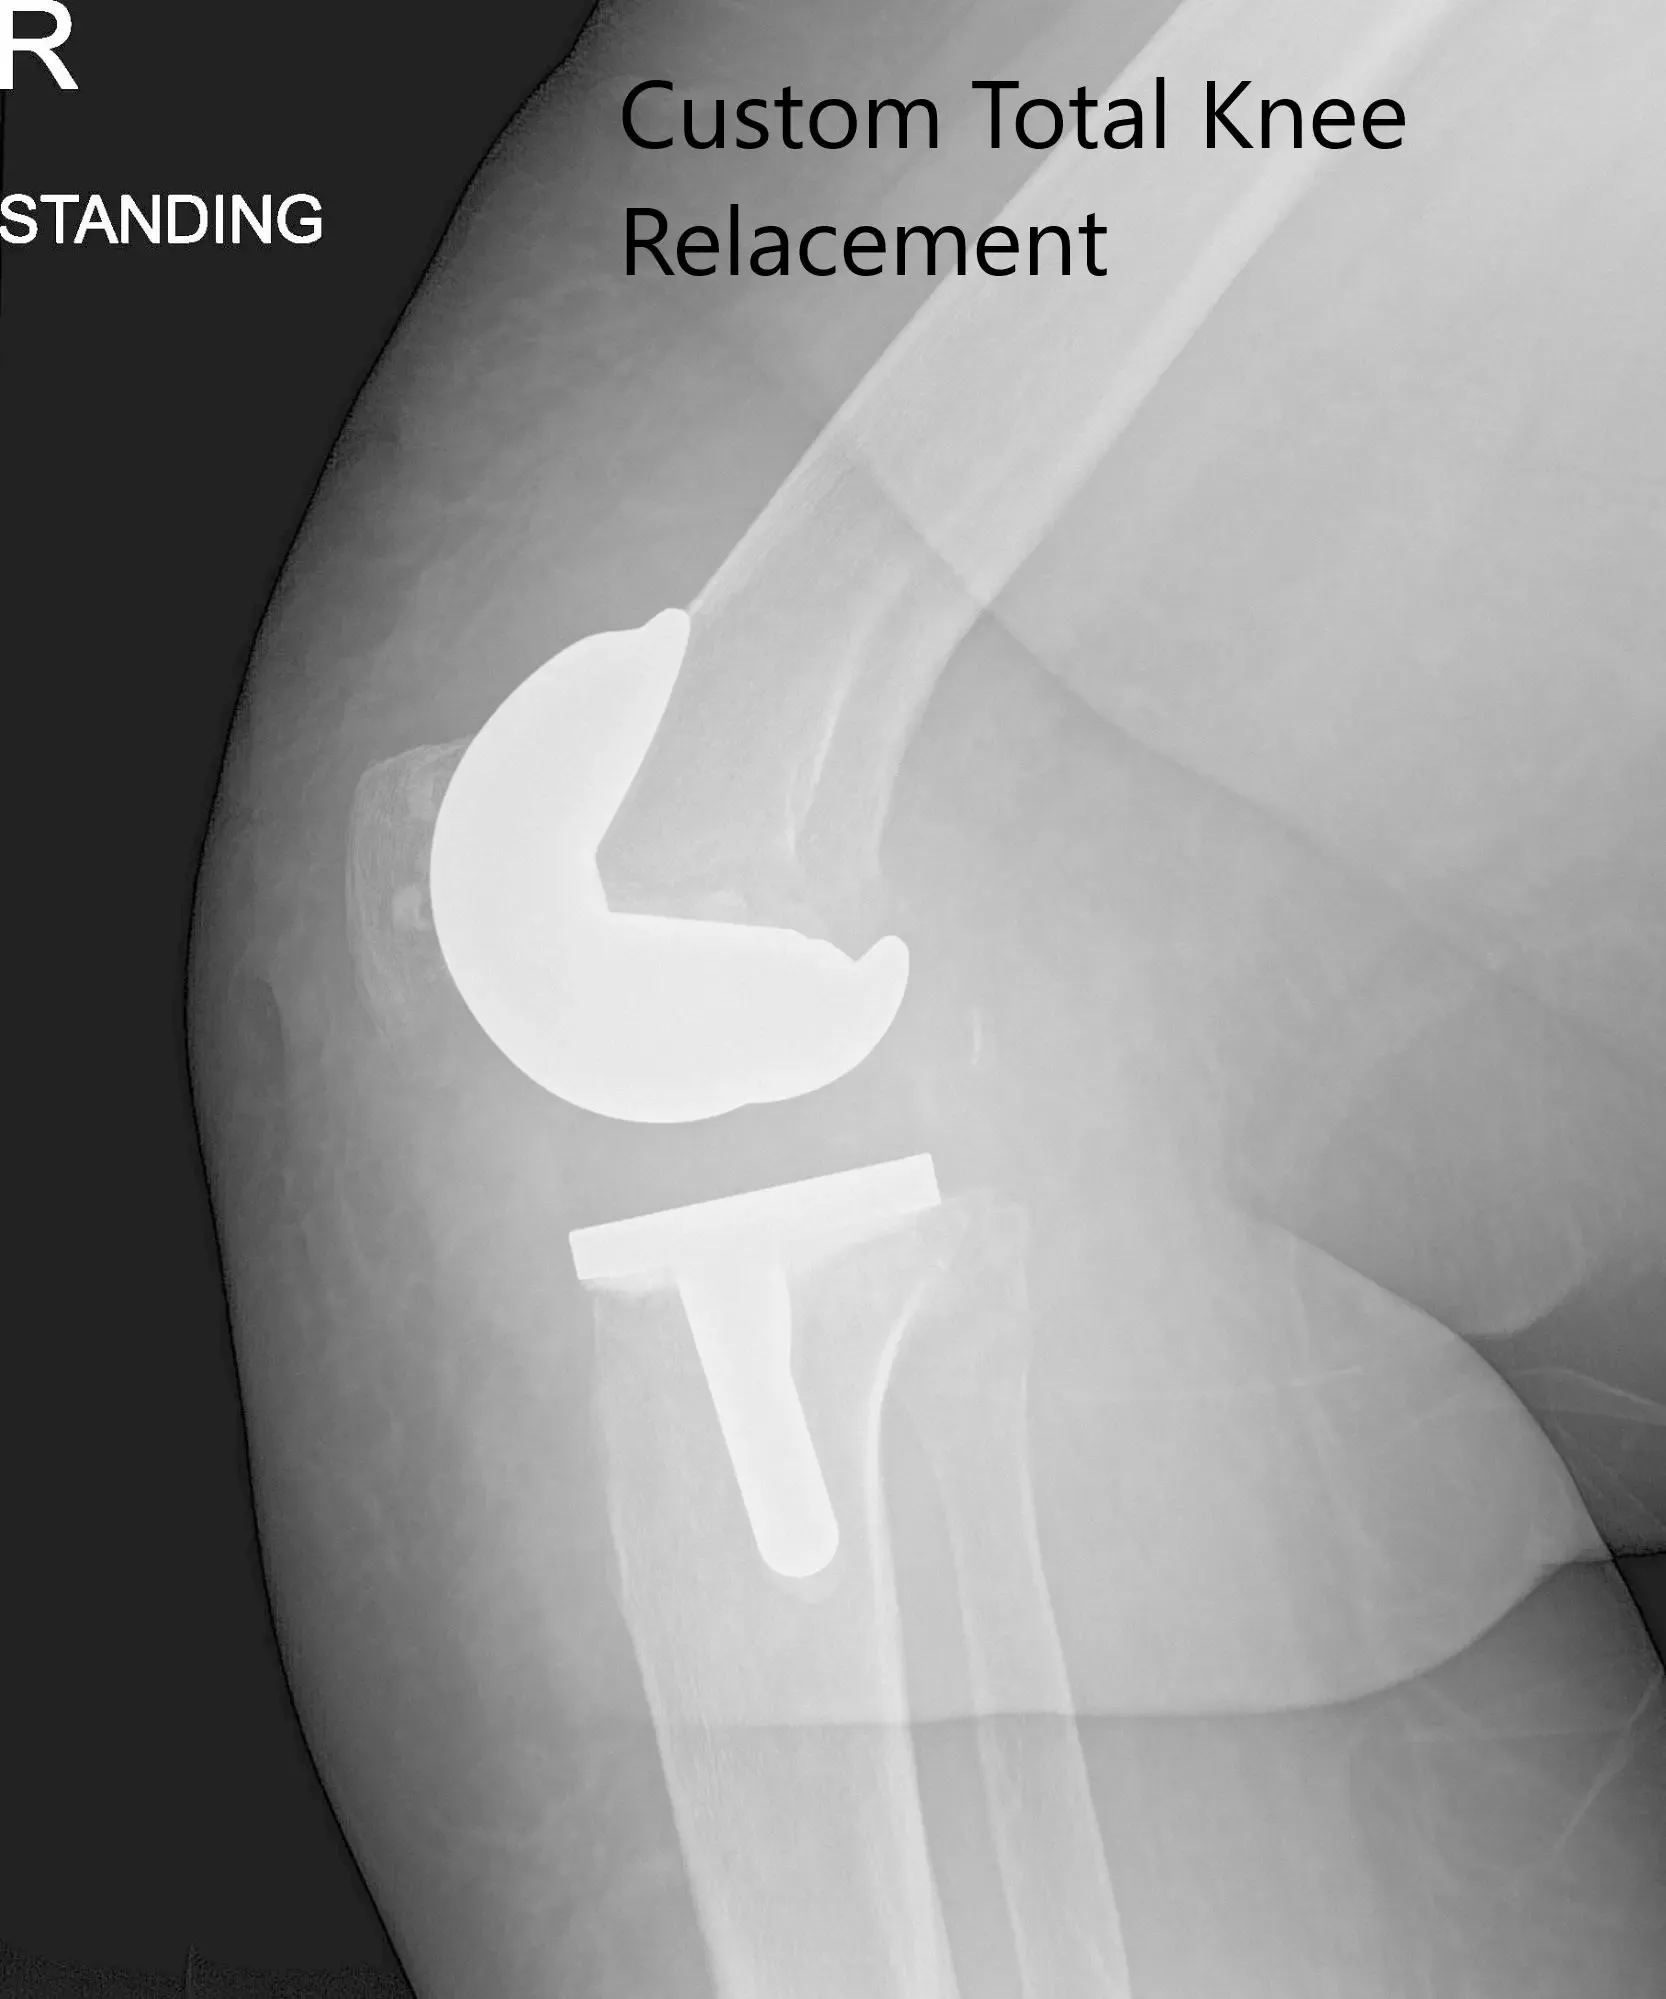

Imágenes de radiografía postoperatorias que muestran la AP y las vistas laterales de la rodilla derecha

Su radiografía postoperatoria mostró una excelente alineación. Se inició fisioterapia ambulatoria para aumentar el rango de movimiento y fortalecer los músculos. En una visita de seguimiento posterior, no mostró dolor ni con un rango de movimiento completo. Volvió a sus actividades habituales y expresó satisfacción por el resultado de la cirugía. Ella hace un seguimiento cuando es necesario.